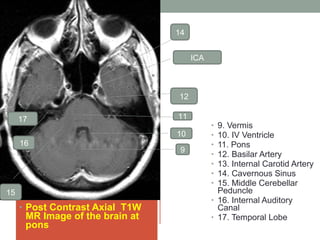

• Post Contrast Axial T1W

MR Image of the brain at

pons

• 9. Vermis

• 10. IV Ventricle

• 11. Pons

• 12. Basilar Artery

• 13. Internal Carotid Artery

• 14. Cavernous Sinus

• 15. Middle Cerebellar

Peduncle

• 16. Internal Auditory

Canal

• 17. Temporal Lobe

• Post ContrastAxial T1W MR Image of the brain at pons • 9. Vermis • 10. IV Ventricle • 11. Pons • 12. Basilar Artery • 13. Internal Carotid Artery • 14. Cavernous Sinus • 15. Middle Cerebellar Peduncle • 16. Internal Auditory Canal • 17. Temporal Lobe 9 ICA 10 11 12 14 15 16 17